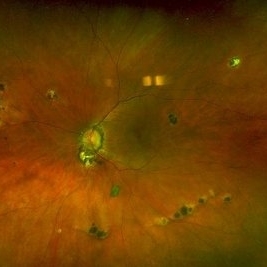

Histoplasmosis Capsulatum Retinitis OS

Histoplasmosis Capsulatum Retinitis OS

Dec 20 2021 by Brad Lovelace

Color SLO image OD of a 63-year-old woman with presumed ocular histoplasmosis syndrome OS observed for change.

Photographer: Cathy Harsma, COA

Imaging device: Optos Ultra-Widefield

Condition/keywords: histoplasmosis, presumed ocular histoplasmosis syndrome (POHS)